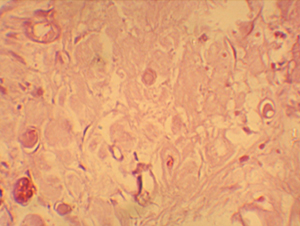

(figura Nº 3). Se encontraron varios glóbulos de adhesivo dispersos en el

tejido pulpar, rodeados por macrófagos (figuras Nº 4 y 5). Las características

histopatológicas observadas en las muestras de este grupo mostraron un estado

inflamatorio crónico en proceso de necrosis, que se extiende inclusive a zonas

distantes del área del recubrimiento.

Figura

N 4.-

Corte Histológico del grupo # 1.

Se encontraron varios glóbulos de adhesivo,

inmersos en el tejido pulpar, rodeados por macrófagos. El proceso

inflamatorio crónico, que se extiende inclusive hasta un milímetro de

distancia del recubrimiento en el tejido conectivo. 400 X |

N 5.-

Acercamiento

de la figura anterior en donde se aprecia un glóbulo de adhesivo inmerso

en el tejido pulpar, rodeado por macrófagos. 1000 X |